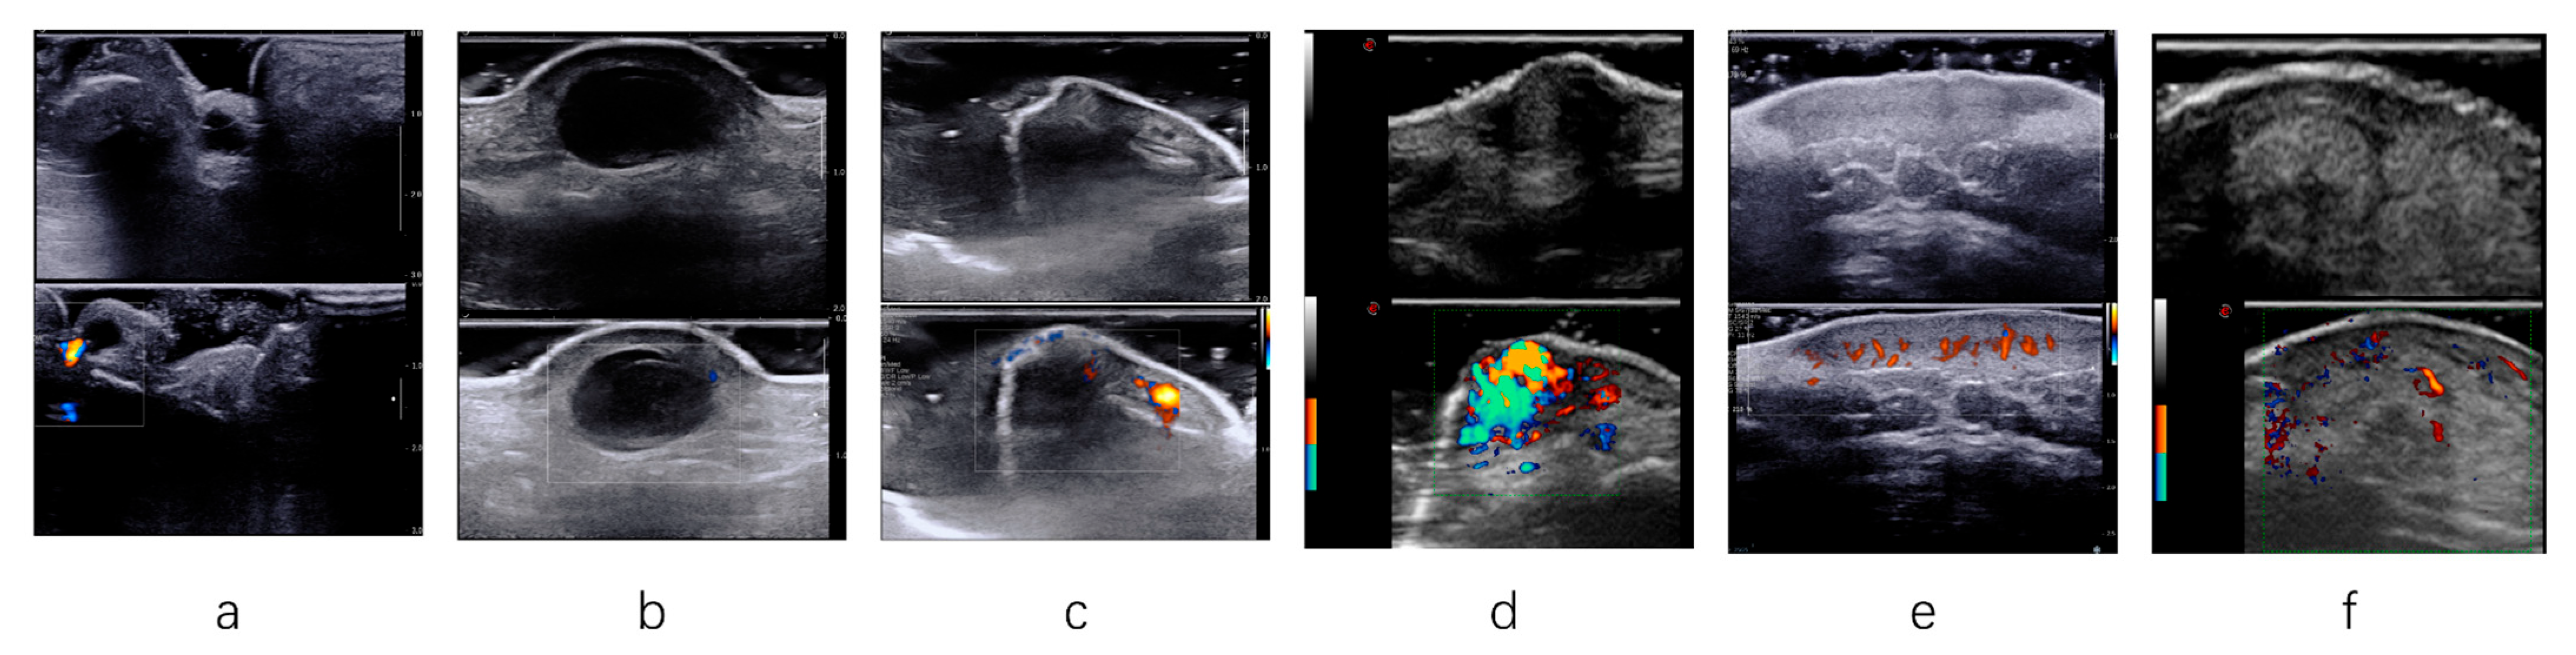

- Having grayscale images, color Doppler flow imaging (CDFI), and dynamic scanning images simultaneously;

- CDFI parameters were also adjusted to suppress noise artifacts and display color Doppler flow signals.

- Mode B: the combination of clinical information and HFUS image information, which includes assessing the lesion’s size, boundary clarity, internal echo characteristics, the characteristics of the skin layer, the involved range of the lesion, and CDFI features.